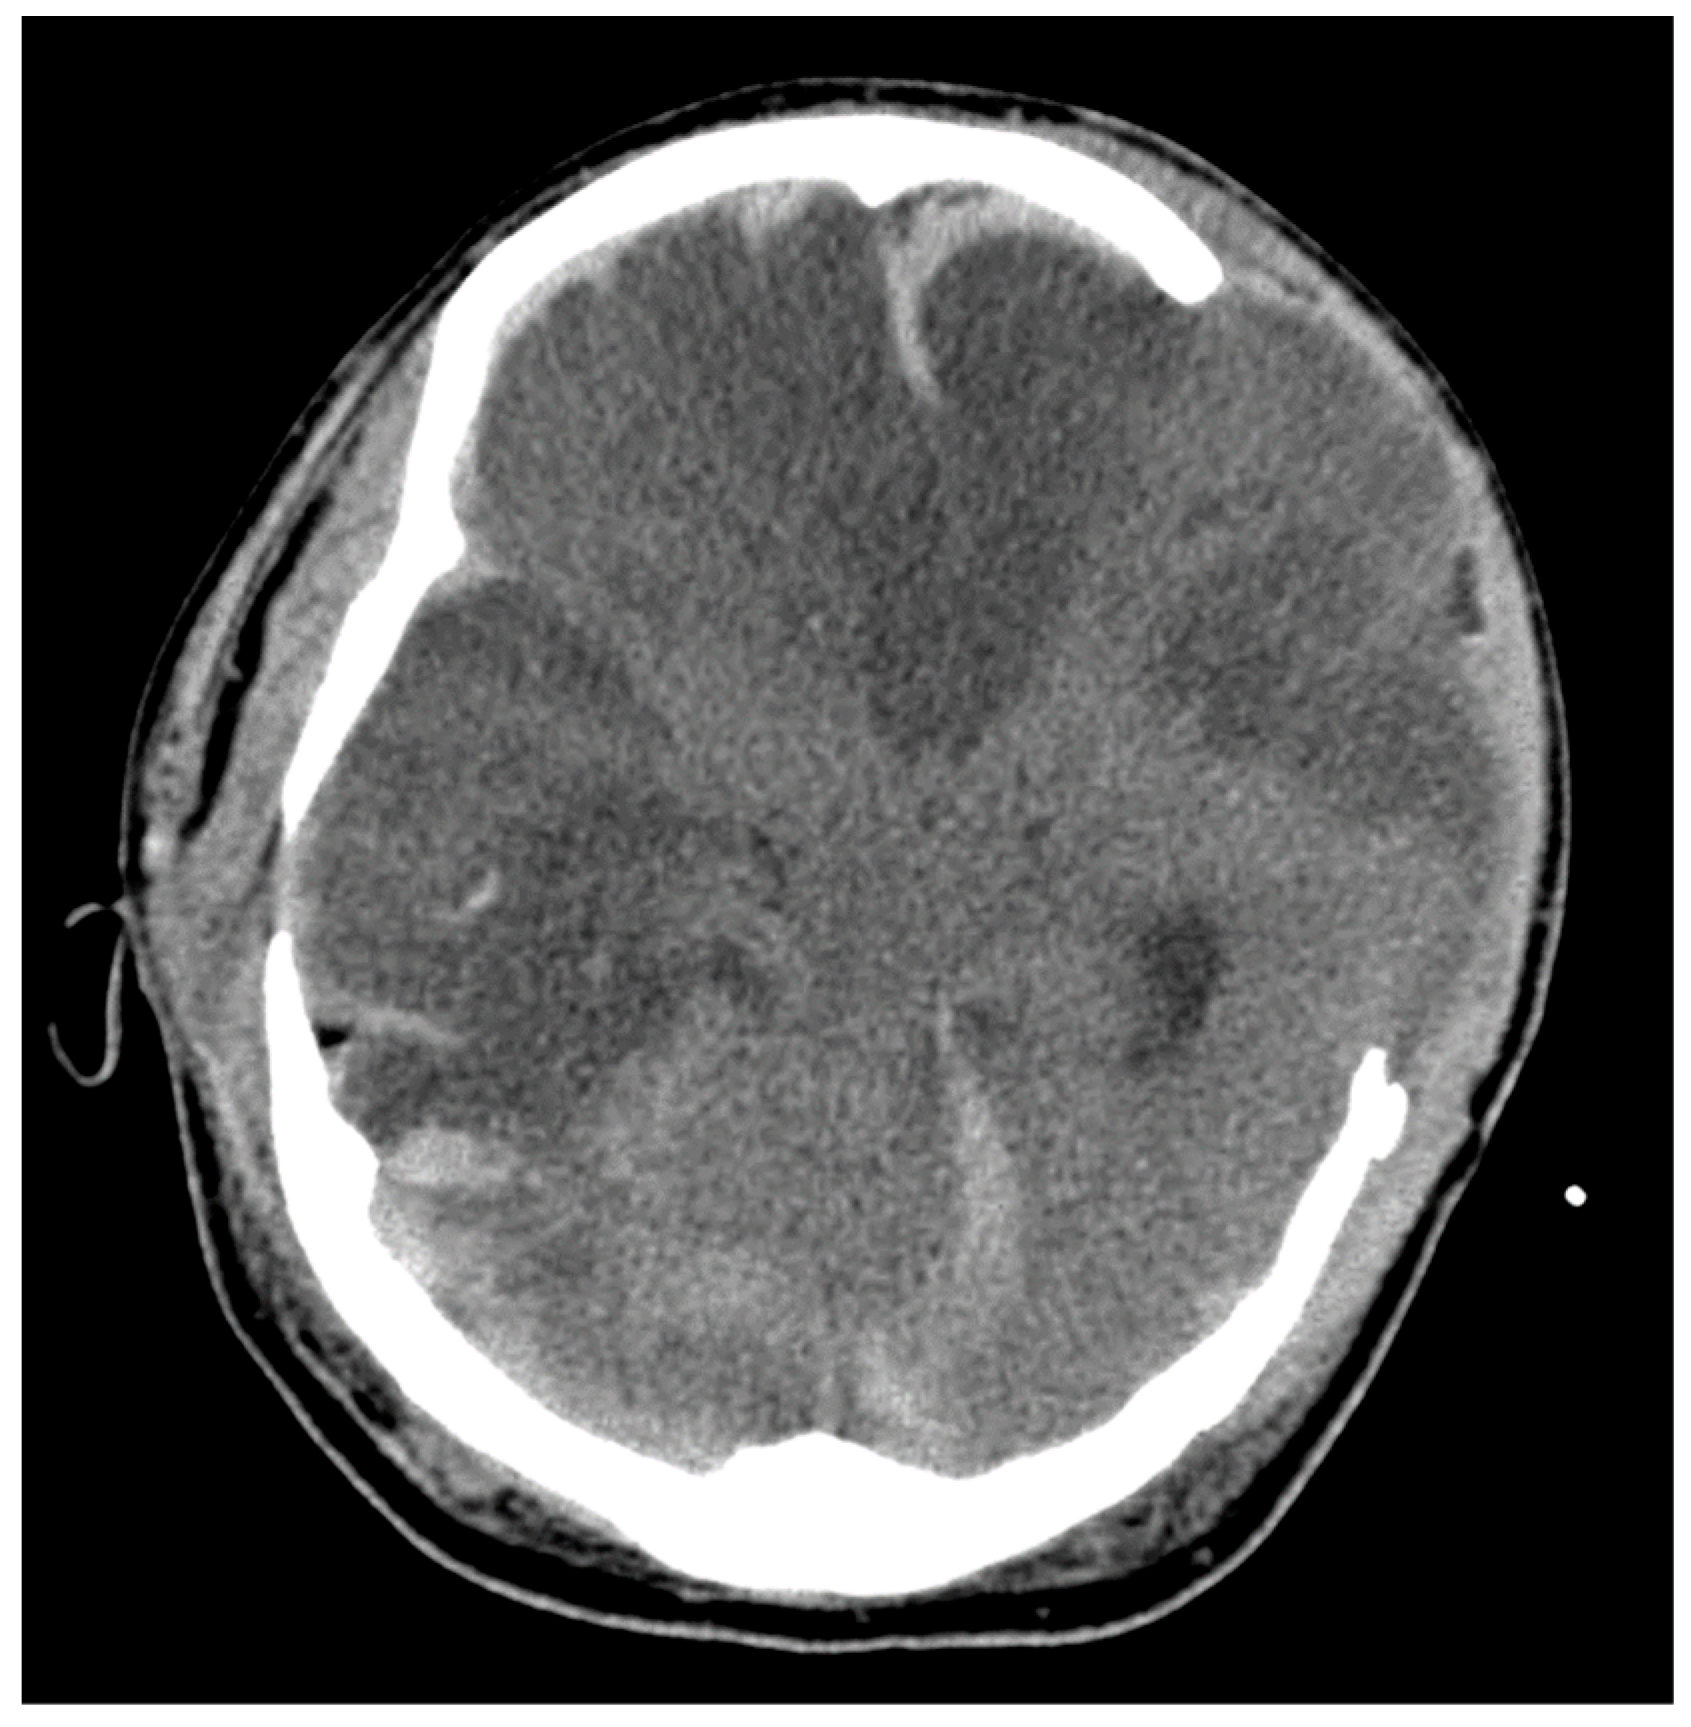

2.2. Brain Herniation

- Wernick, S.; Wells, R.G. Sequelae of temporal lobe herniation: MR imaging. J. Comput. Assist. Tomogr. 1989, 13, 323–325. [Google Scholar] [CrossRef] [PubMed]

- Rothfus, W.E.; Goldberg, A.L.; Tabas, J.H.; Deeb, Z.L. Callosomarginal infarction secondary to transfalcial herniation. AJNR Am. J. Neuroradiol. 1987, 8, 1073–1076. [Google Scholar] [PubMed]